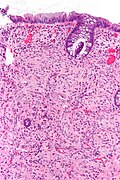

Microscopic

Features:

- Test tube like glands.

- Minimal palisading.

- Nuclei <3:1 = height:width.

- No nuclear pseudostratification. †

- Deep part of crypt is more hyperchromatic than superficial component - important.

- The surface should be lighter staining than the deeper aspect, i.e. the deeper glands are dark blue and the superficial gland are light blue.

Images

- Rectum - low mag.jpg

Rectum - low mag. (WC)

- Rectum - intermed mag.jpg

Rectum - intermed. mag. (WC)

- Rectum - alt - intermed mag.jpg

- Rectum - high mag.jpg

Rectum - high mag. (WC)